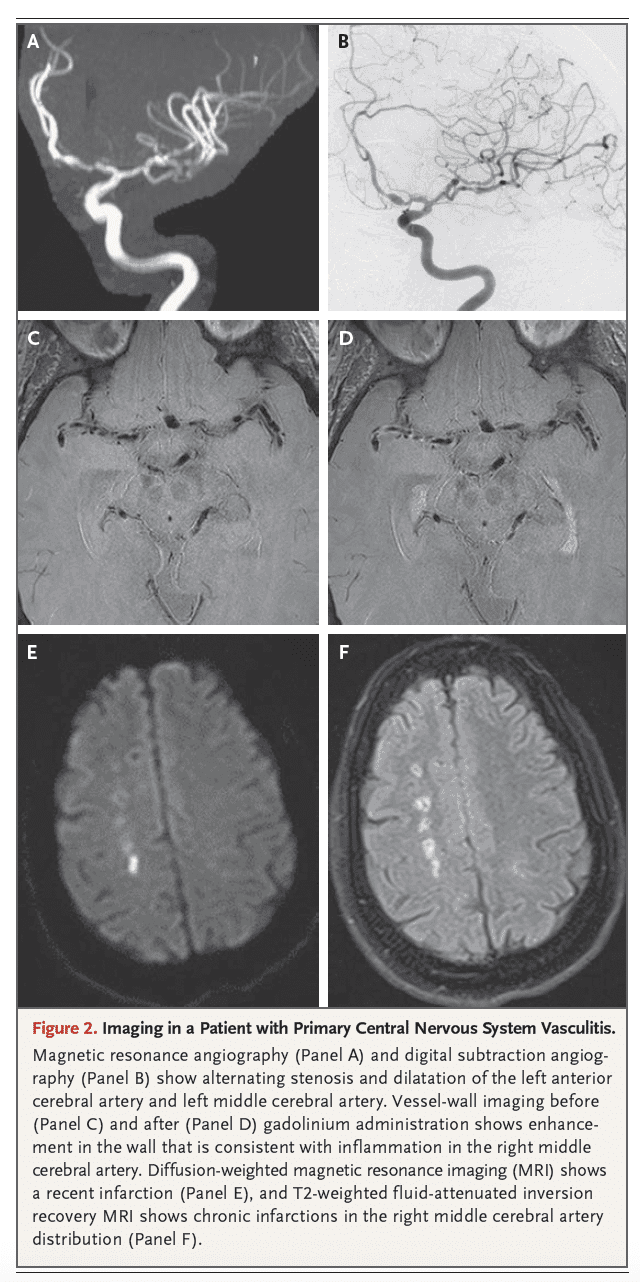

Figura 2: Imagens em um Paciente com Vasculite Primária do Sistema Nervoso Central

Esta figura apresenta imagens de ressonância magnética (RM) e angiografia em um paciente com VPSNC:

- Painéis A e B: Angiografia por ressonância magnética (ARM) e angiografia por subtração digital (ASD) mostram estenose e dilatação alternadas da artéria cerebral anterior esquerda e da artéria cerebral média esquerda. Essas imagens demonstram a alteração característica da parede vascular em um padrão segmentar.

- Painéis C e D: Imagens de parede vascular em RM de alta resolução antes (C) e depois (D) da administração de gadolínio mostram realce na parede vascular, consistente com inflamação na artéria cerebral média direita. Isso evidencia a inflamação da parede vascular.

- Painel E: Imagem de RM com ponderação de difusão mostra um infarto recente.

- Painel F: Imagem de RM ponderada em T2 com supressão de líquido mostra infartos crônicos na distribuição da artéria cerebral média direita. As lesões antigas são evidenciadas pela alteração de sinal crônico.